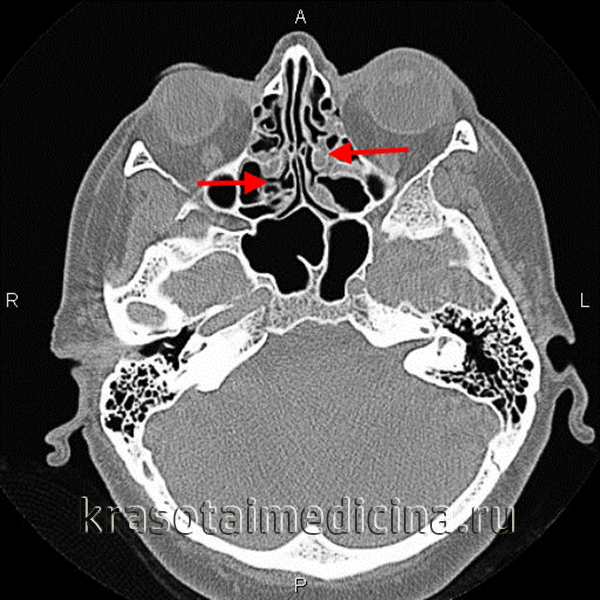

- Томография.Компьютерная томография синусов используется при низкой информативности рентгенографии, признаках орбитальных или внутричерепных осложнений. Кроме того, исследование применяется для достоверной дифференциальной диагностики с другими патологиями. При необходимости сочетается с МРТ придаточных пазух носа.

1) Компьютерная томография (КТ) позволит определить степень воспаления решетчатого синуса, наличие в нем полипов, гноя. Особенно, ее важно провести, если у пациента есть симптомы, говорящие о распространении инфекции в область глазниц или других придаточных пазух носа.

Диагностика этмоидита может составлять определенные сложности, учитывая расположение решетчатой кости, высокую частоту смешанных форм и возможное доминирование симптоматики основного заболевания. Необходим тщательный учет и сопоставление анамнеза, жалоб, результатов рино-, ото-, фарингоскопии, данных лабораторного и дополнительного инструментального исследований. Стандартом визуализации долгое время оставалась рентгенография, однако диагностические возможности и информативность томографических методов значительно выше, поэтому предпочтительным является КТ или МРТ.